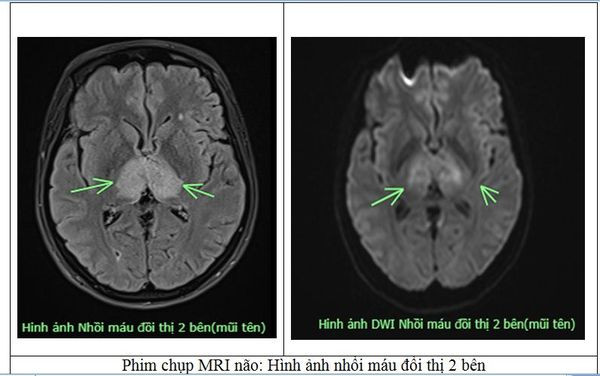

Người bệnh nữ, 38 tuổi, trú tại xã Sơn Hùng, huyện Thanh Sơn, Tỉnh Phú Thọ. Trước vào viện 4 ngày, người bệnh xuất hiện đau đầu, tự uống thuốc tại nhà nhưng không đỡ, sau đó ý thức chậm hơn, được gia đình đưa vào Bệnh viện Đa khoa tỉnh Phú Thọ trong tình trạng ý thức chậm chạp, Glasgow 13 điểm, tự thở, yếu tứ chi. Người bệnh được các bác sĩ chỉ định chụp MRI, kết quả có hình ảnh nhồi máu não tại vị trí đồi thị 2 bên.

Nhận thấy nhồi máu đồi thị 2 bên là tổn thương khá bất thường, các bác sĩ của Trung tâm Đột quỵ đã hội chẩn và đặt ra nghi vấn về 1 bệnh lý khá hiếm gặp, bệnh lý “Huyết khối tĩnh mạch não”.

Người bệnh được chỉ định chụp MRI sọ não có dựng xoang tĩnh mạch (TOP2D), xét nghiệm đông máu D-dimer. Kết quả xác định đây là 1 trường hợp “Huyết khối tĩnh mạch não”.

Kết luận: Hình ảnh huyết khối tĩnh mạch xoang ngang phải, xoang dọc trên, tĩnh mạch xoang thẳng lan theo tĩnh mạch não lớn và tĩnh mạch đồi thị hai bên, có phù não đồi thị hai bên và ổ thiếu máu não đồi thị phải.